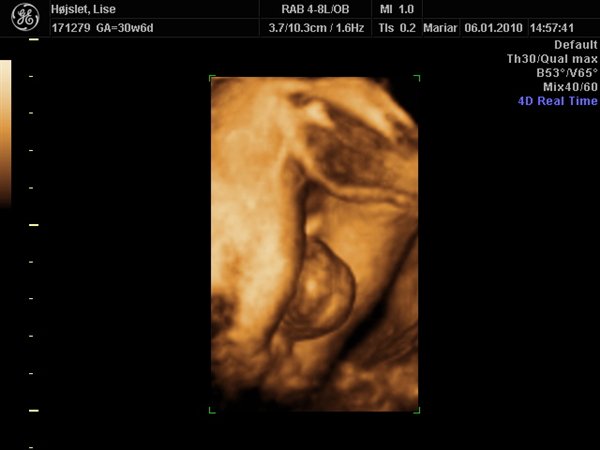

Lise

Her er der vist ingen tvivl

Vedhæftede fotos (klik for at se i fuld størrelse)

ville blive MEGET overrasket hvis der kommer en pige udaf det billed der